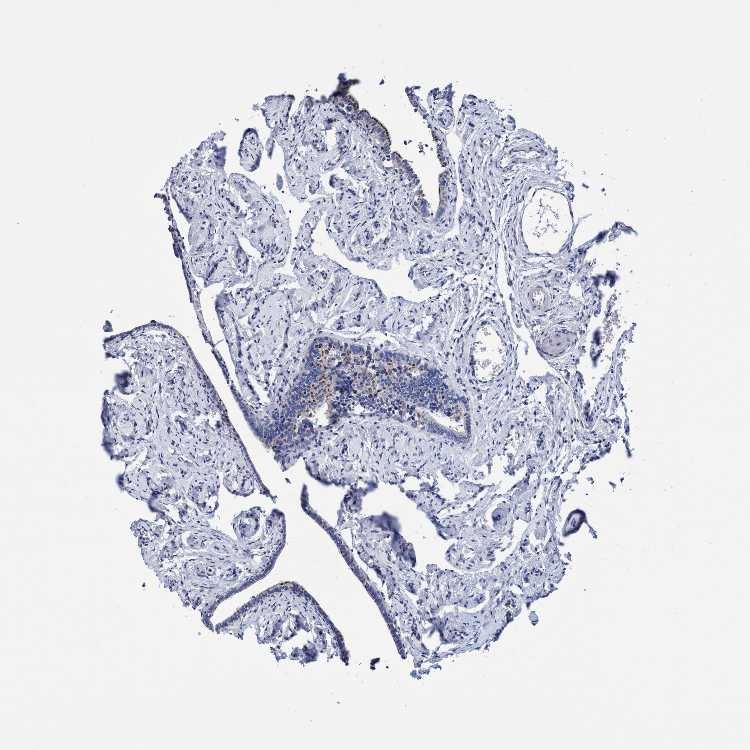

CROCC